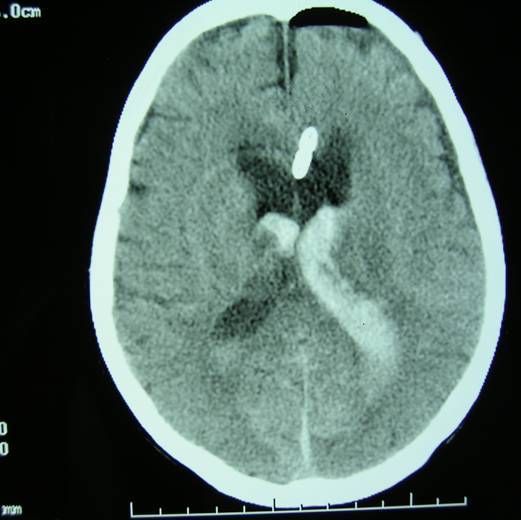

我们采用侧脑室穿刺外引流术,尿激酶脑室内注入,每日一次加腰穿释放脑脊液治疗。效果较好。

术前

术后